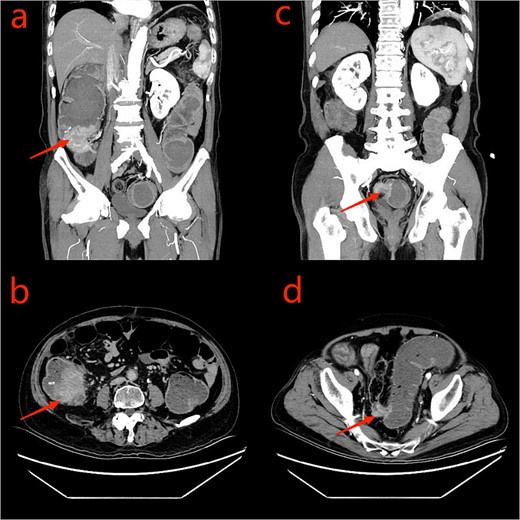

Given the patient’s unsuitability for immediate radical surgical resection, the patient was administered monotherapy with capecitabine to control tumor progression. During an outpatient follow-up, a slight enlargement of the tumor was observed in the ascending colon region. To further understand the patient’s condition, he was readmitted to the hospital, to undergo laboratory tests, serum CEA: 26.10 ng/ml, uric acid: 447 umol/L, and platelet levels were normal. Repeated enhanced CT scanning of the abdomen revealed complete recovery from the obstruction (Fig. 3). To ascertain the nature of the ascending colon tumor,a repeat colonoscopy examination through colostomy showed the sigmoid and ascending colon tumor. The biopsy of the ascending colon tumor revealed an adenocarcinoma (Fig. 4). Given the patient’s concomitant small B-cell lymphoma and primary thrombocytopenia, surgical treatment was decided after a multi-disciplinary team discussion.

CT scan of the abdomen and pelvis: a and b: ascending colon tumor; c and d: sigmoid tumor.